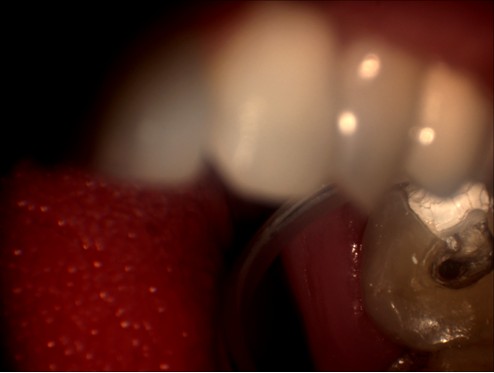

明美工程師在剛開始接觸牙科專用顯微鏡時,對這臺牙科專用顯微鏡有點陌生。牙科專用顯微鏡與其他的顯微鏡有點不同,1米多高的機身,沒有粗微調,調焦只能通過手動上下移動來實行。在安裝過程中遇到了很多技術上的難題,如顯微鏡的接口問題,這款顯微鏡的C接口并不是標準的C型接口,有點偏小。經過我們工程師專業(yè)的技術經驗及反復試驗,發(fā)現(xiàn)在它原有的接口的基礎上再接上準的C型接口,即接兩個C接口就能把顯微鏡相機安接裝上去。但是安裝上去并不能完解決此問題,還有成像方面的問題,由于它原有的C接口不是標準的C口,在實拍的時候,可以達到同步的效果,而且靜態(tài)拍攝圖片效果不錯,但在實際口腔內拍攝的時候圖像太暗,若只通過軟件調節(jié)后,亮度達到了,但是有點反光,通過和技術人員溝通后,發(fā)現(xiàn)那臺顯微鏡用的是一個普通的照明燈,亮度不可調,通過幾番周折后,通過調試后亮度問題終于解決。明美工程師在順利安裝完成了,楊主任對此效果表示滿意,亦對明美工程師的專業(yè)技術能力給予肯定。以下為顯微鏡相機實拍圖片:

顯微圖片

牙科顯微圖片